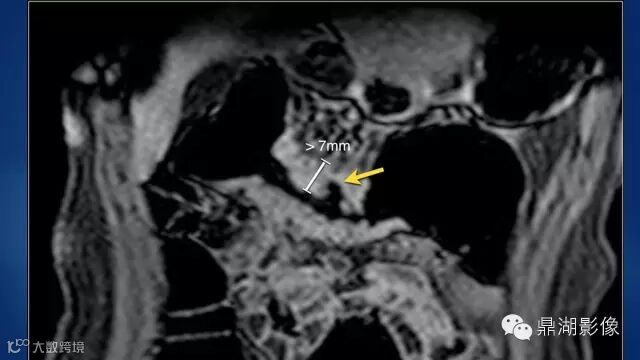

do you know comb sign?

The comb sign refers to the hypervascular appearance of the mesentery in active Crohn disease.